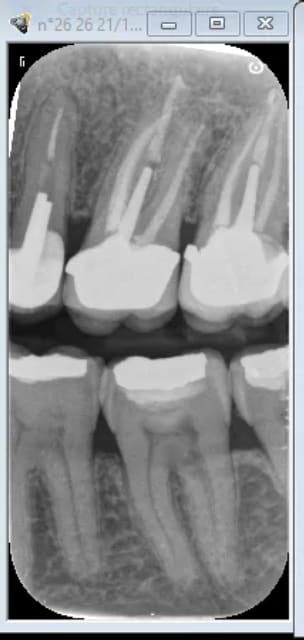

Tiens status meilleur rapport qualité - prix capteur taille 2 isensor woodpecker 1500 balles camera MD960 150 balles. Qui dit mieux ?

Q7hzhmdtbcm7o90tyozq57rg5b05 - Eugenol

CS 6200 VS I sensor wood pecker

--

U1hmcyehazycn2ogu4ihlnk89fs9 - Eugenol

01/04/2024 à 05h55

Tu peux faire ça aussi.

Ztazqvfo0icuajk94i1s5e4ijsx6 - Eugenol

Cherchez l'erreur.

W5hwweso1i5f9e2gccviwihkyxxi - Eugenol

Capteur.

Capture d  cran 2015 03 12 12.28 - Eugenol

Plaque . -)